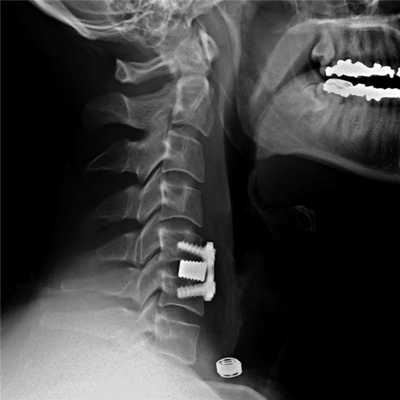

Эндопротезирование межпозвоночного диска

Цервикальный эндопротез может заменить исходную форму межпозвоночного диска. © Spinal Kinetics

на протяжении десяти лет искусственные межпозвоночные диски являются эффективной и распространённой методикой лечения. Кроме того, эта операция является еще и многообещающей альтернативой зарекомендовавшему себя спондилодезу - операции, блокирующей тела отдельных позвонков. Так же эндопротезирование межпозвоночного диска направлено на восстановление природных функций межпозвонкового диска. Целью данного хирургического вмешательства является ослабление либо нормализация симптоматики, связанной с дегенерацией межпозвоночных дисков и грыжей, например хронических болей в спине и неврологических нарушений. Эндопротез заменяет настоящий межпозвоночный диск, стабилизирует позвоночник и защищает его от последующих травм. В медицинской центре Геленк-Клиник во время данной операции используются протезы типа M6-C. Такие дисковые протезы держаться на протяжении всей жизни и не нуждаются в замене.

На шейных уровнях применяются и стабилизирующие тактики оперативных вмешательств, каждая из которых, кстати, может идти совместно и с другими видами операций. Наиболее популярные из стабилизирующих методов:

- - неподвижное соединение (сращивание) двух или более позвонков при их нестабильности;

Импланты шейного отдела позвоночника на рентгене.

Если клиника симптомов не поддается консервативной терапии или неинвазивные способы не могут быть задействованными ввиду сильно прогрессирующего стеноза, назначается операция. Вмешательство предполагает использование декомпрессионной ламинэктомии под общим наркозом. При комбинированной проблеме, например, вместе с грыжей, ее сочетают с микродискэктомией и спондилодезом. При спондилодезе осуществляют скрепление смежных позвонков металлическими фиксаторами (стержнями, пластинами, крючками и пр.), установку межтеловых имплантатов или вживление костного трансплантата с металлической гильзой.

Установка металлической конструкции.